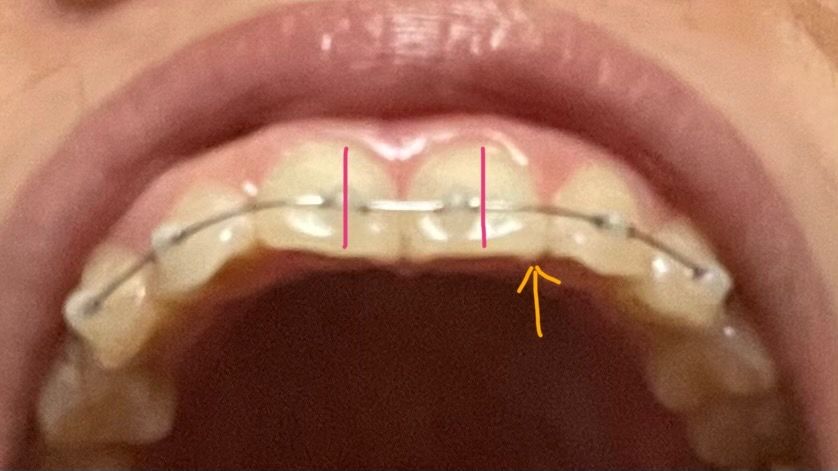

교정시작할때 위앞니 하나는 원래 실금(craze line) 있는거 인지하고 시작했는데

나머지 윗앞니 하나에 몇일전부터 선이 시작되더니 일자로 쭉 내려오네요.

4. 사진처럼 세로로 실금이 있고 교정하면서 화살표(뒷면 통통한부분) 부분이 아랫니랑 맞닿기시작했는데 실금에 영향은 없을까요?

• 1번 째 사진